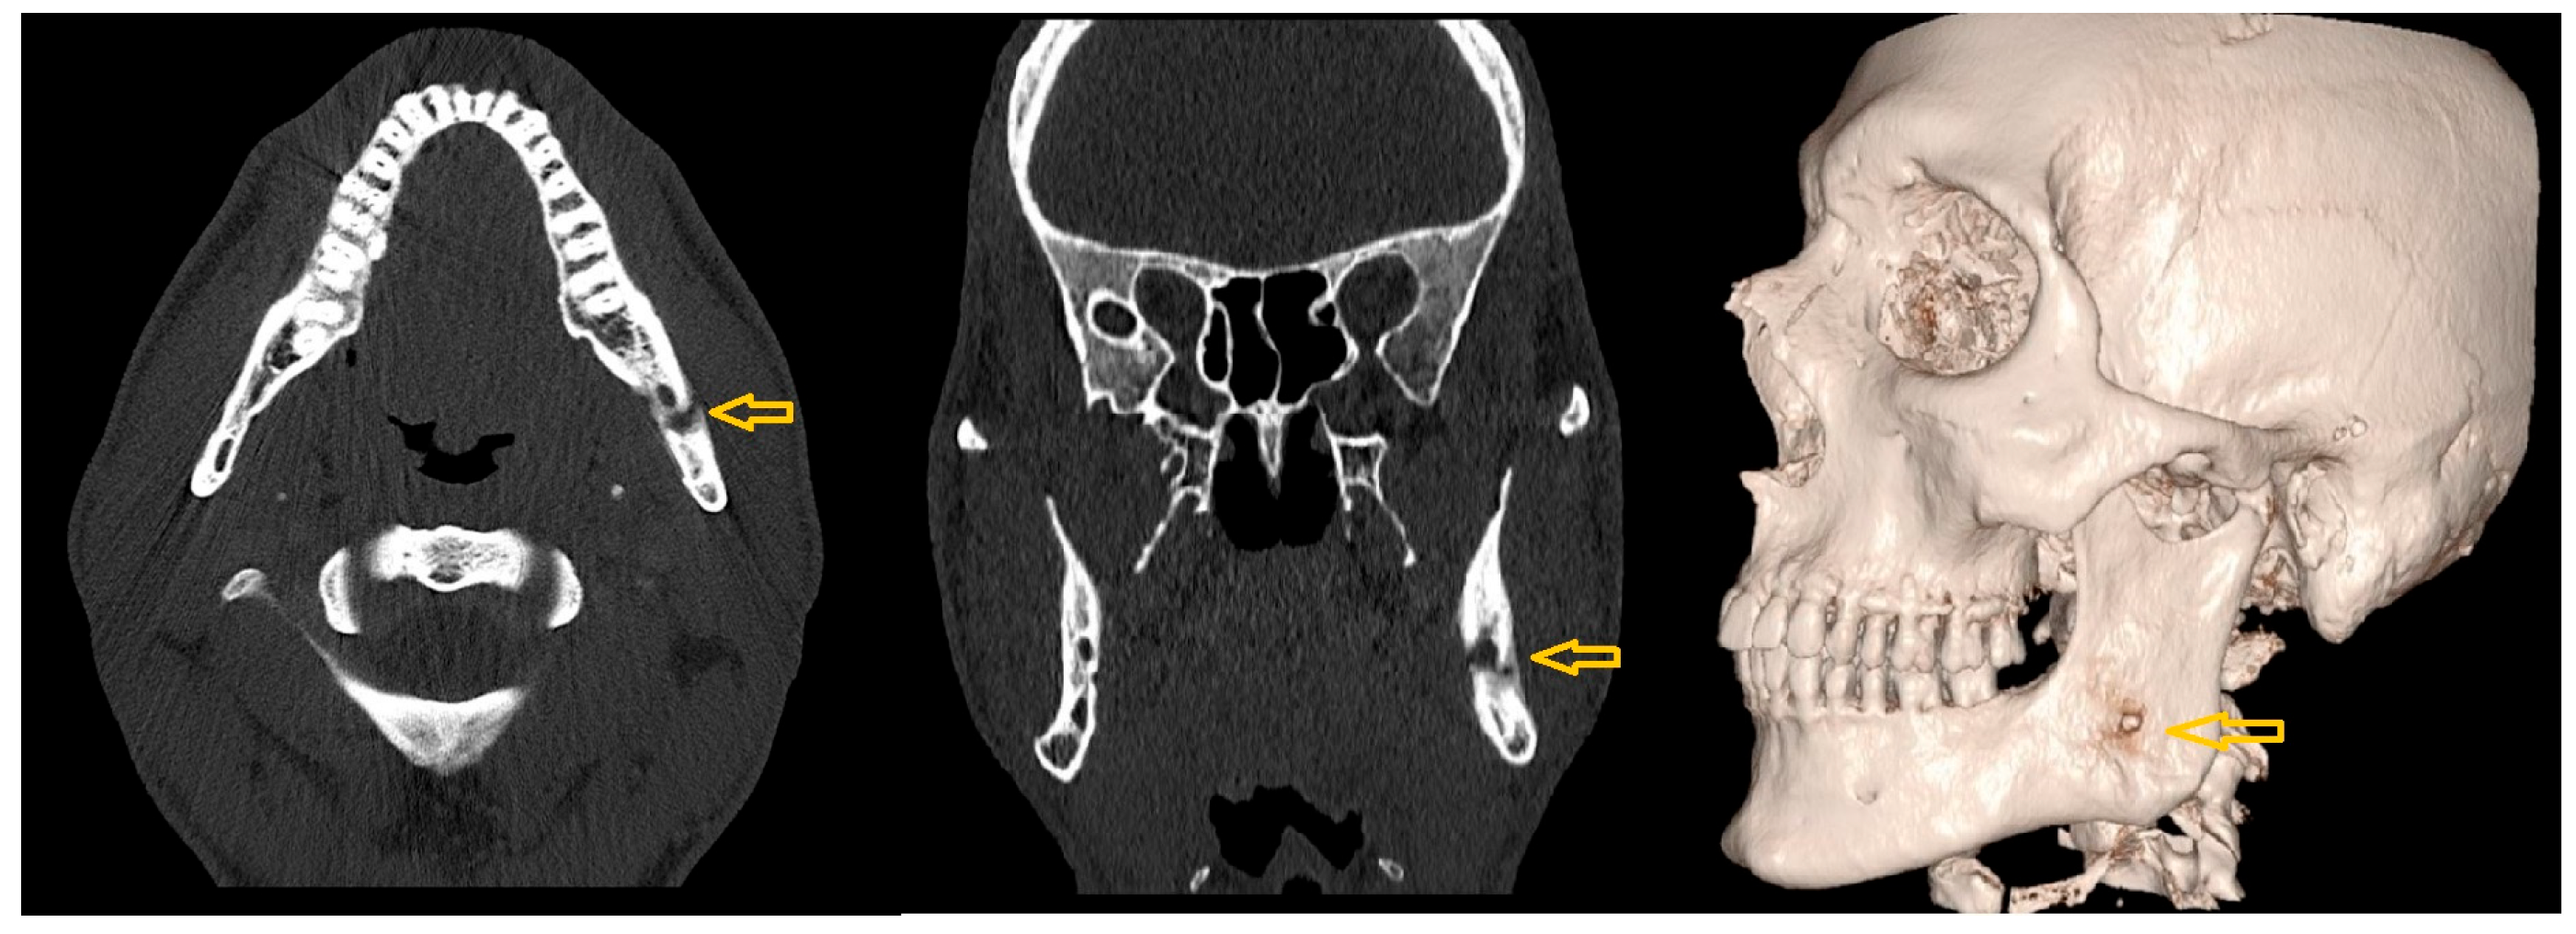

- Case 1

- Case 2